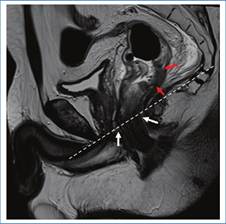

Se debe determinar con certeza si la lesión se encuentra a nivel rectal o en el colon sigmoides, ya que en ambos casos existe un abordaje quirúrgico distinto3. Uno de los métodos más utilizados por las guías internacionales para la definición de tumor de recto es la medición de la distancia entre la porción distal de este y el margen anal, considerando a todos aquellos tumores ubicados a una distancia ≤ 15 cm del margen anal como tumor rectal. A su vez, se los subclasifica en tumores de recto superior, medio y/o inferior (Fig. 2)3),(4),(5. El recto es un órgano con una porción intraperitoneal y otra extraperitoneal, que pueden ser diferenciadas mediante la identificación de una fina membrana hipointensa en T2 correspondiente a la reflexión peritoneal anterior. Esta suele visualizarse en el plano sagital y une las vesículas seminales en el hombre y el fondo de saco de Douglas en la mujer, con la cara anterior del recto medio (Fig. 3)3,6. Por encima de esta, el peritoneo recubre las caras anterior y lateral del recto superior y la cara anterior del recto medio, mientras que el recto inferior es completamente extraperitoneal6. A su vez, la FMR rodea completamente al mesorrecto por debajo de la reflexión peritoneal y por su caras laterales y posteriores por encima de esta3 (Fig. 4).

En sentido caudal, debemos identificar la unión ano-rectal y el margen anal, para de esa forma identificar el canal anal. Esta unión ano-rectal se encuentra en íntima relación con el anillo puborrectal y la porción proximal del esfínter anal externo, para identificar esta se toma como punto de referencia una línea imaginaria que une la cara inferior del pubis y el sacro3 (Fig. 5).